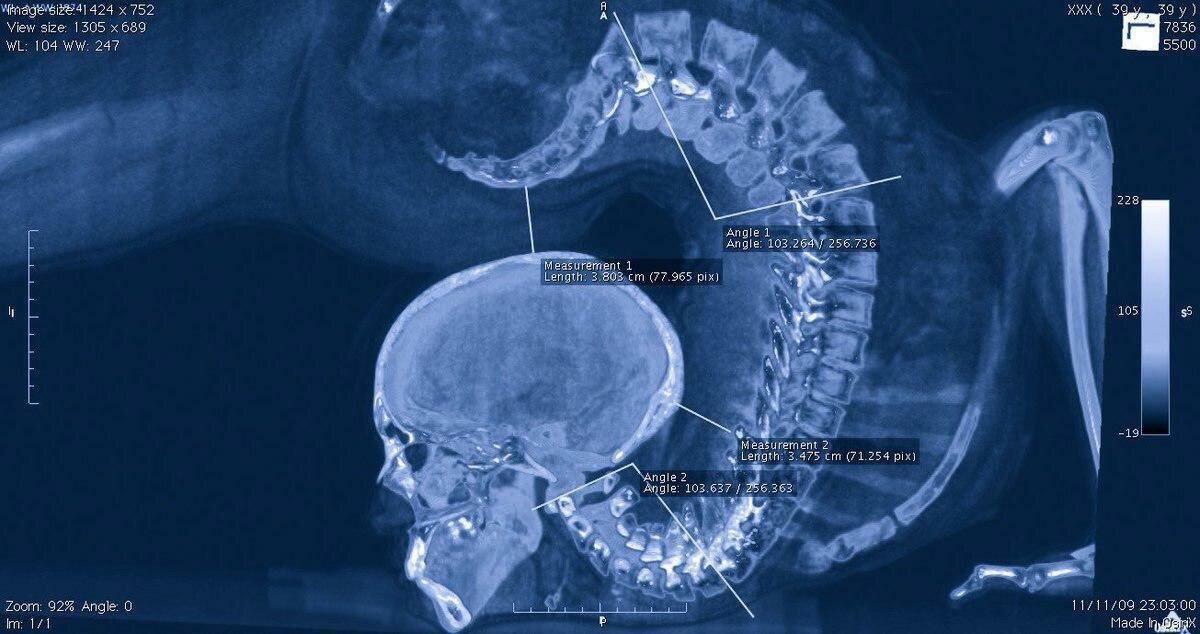

Нудим дальше. Даже если вы не полезли в справочник физиологии, посмотрите на иллюстрацию к статье, на обе картинки. Обратите внимание на то, что между отростками позвонков есть мяско, ваши мягкие ткани — мышцы, связки. Еще важнейший момент — обратите внимание на соотношение размеров позвонков и толщины и размера межпозвонкового диска — он, кстати, не работает как резинка. Его нельзя растянуть так, чтобы он обратно укоротился. Его можно растянуть только до протрузии, а потом до грыжи. Других вариантов нет.

А теперь внимательно изучаем снимок, где голова на попе. Посмотрите сами, что именно и где там растянуто или уже разорвано, и только представьте, где буквально раздавлены отростками мягкие ткани.

Пресловутый «грудной отдел», который все всем советуют «раскрывать» просто выпрямлен, шейный — там полный … , прилично назовем, ужас, и он же в поясничном. Список последствий регулярных встреч костей с костями можно перечислять вечно, будущее человека на снимке вариативно, но к сожалению там нет ни одной радужной перспективы. Вот дети или престарелые родители огребут вечно страдающую обузу себе. Тут уж мы ничем не поможем, он уже сделал это.